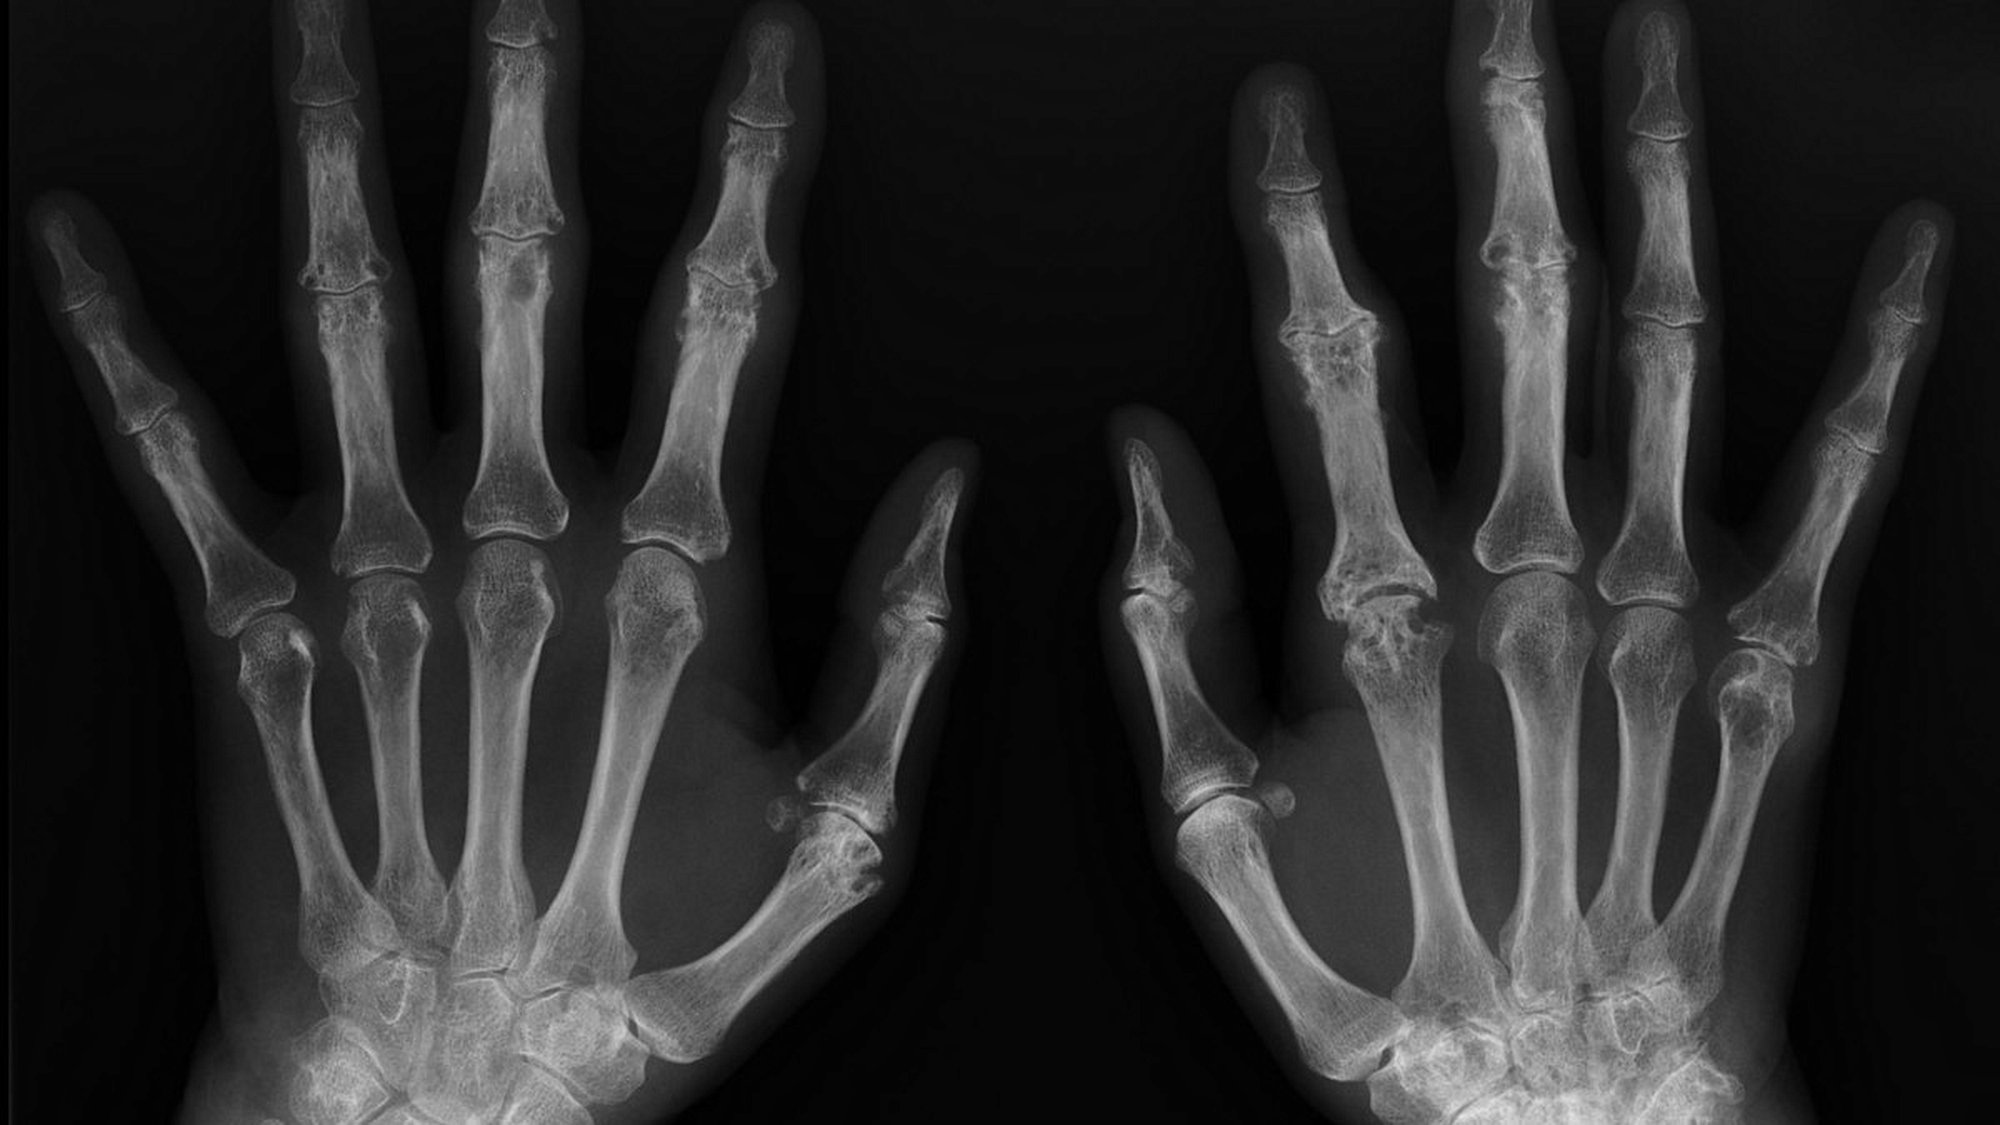

Bebeklikten Yetişkinliğe Ellerimizin X-Işını Görüntüsü ve Kemik Yaşı

Aşağıda gördüğünüz, bir insanın bebekliğinden yetişkinliğine kadar farklı zamanlarda çekilmiş ellerine ait X-Işını Taraması (X-Ray) görüntüleridir.

Bir çocuğun kemiklerinin uçlarında (örneğin parmak ve bilek kemiklerinin uçlarında) "büyüme bölgeleri" olarak da bilinen "büyüme plakaları" bulunur. Bu bölgelerde kemiklerin boylamasına uzamasını sağlayan özelleşmiş hücreler vardır. Bu büyüme plakalarını X-Işını Taraması altında görmek kolaydır, çünkü daha yumuşak yapılıdırlar ve içeriklerinde daha az mineral vardır. Bu da, X-Işını altında diğer dokulara göre daha koyu gözükmelerine neden olur. Görselde, "A" olarak işaretlenmiş fotoğraftaki kemikler arası siyah boşluk bundan kaynaklanır.

Çocuklar büyüdükçe, büyüme plakalarının görünümü de değişir. Giderek daha ince hale gelirler, buna bağlı olarak X-Işını Taraması'nda daha beyaz (yani diğer kemikler gibi) gözükürler ve hatta sonunda tamamen görünmez bile olabilirler. Artık büyük oranda veya tamamen yok olmuş bu plakalara "kapanmış büyüme plakaları" adı verilir. Her bir yaşta farklı gözüktükleri için, sadece kemiklere ve büyüme plakalarına bakarak bir insanın kemik yaşı belirlenebilir. Bunun için doktorlar bir kemik atlasına başvururlar ve söz konusu bireyin plakalarının görünümünün atlastaki hangi kemik yaşına ("iskelet yaşı" olarak da bilinir) denk geldiğini tespit ederler. Böylece bireyin yaşı belirlenebilir.